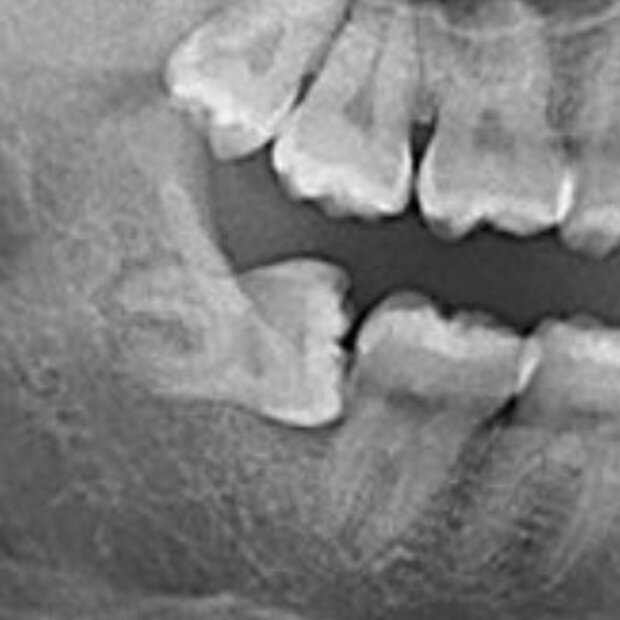

Spesso, per via di una mancanza di spazio o un orientamento scorretto durante la fase eruttiva, il dente del giudizio può andare incontro ad inclusione. L'esame radiologico di base è l'ortopantomografia che viene eseguita direttamente in studio e ci consente di capire nell'immediatezza il grado di inclusione dell'elemento dentario, il suo orientamento e i rapporti che contrae con le strutture anatomiche adiacenti. A seconda del caso, può essere necessario ricorrere ad un esame radiologico tridimensionale per avere informazioni ancora più accurate sulla posizione dell'elemento dentario. La terapia della disodontiasi dei denti del giudizio consiste nell'estrazione chirurgica degli elementi dentari.